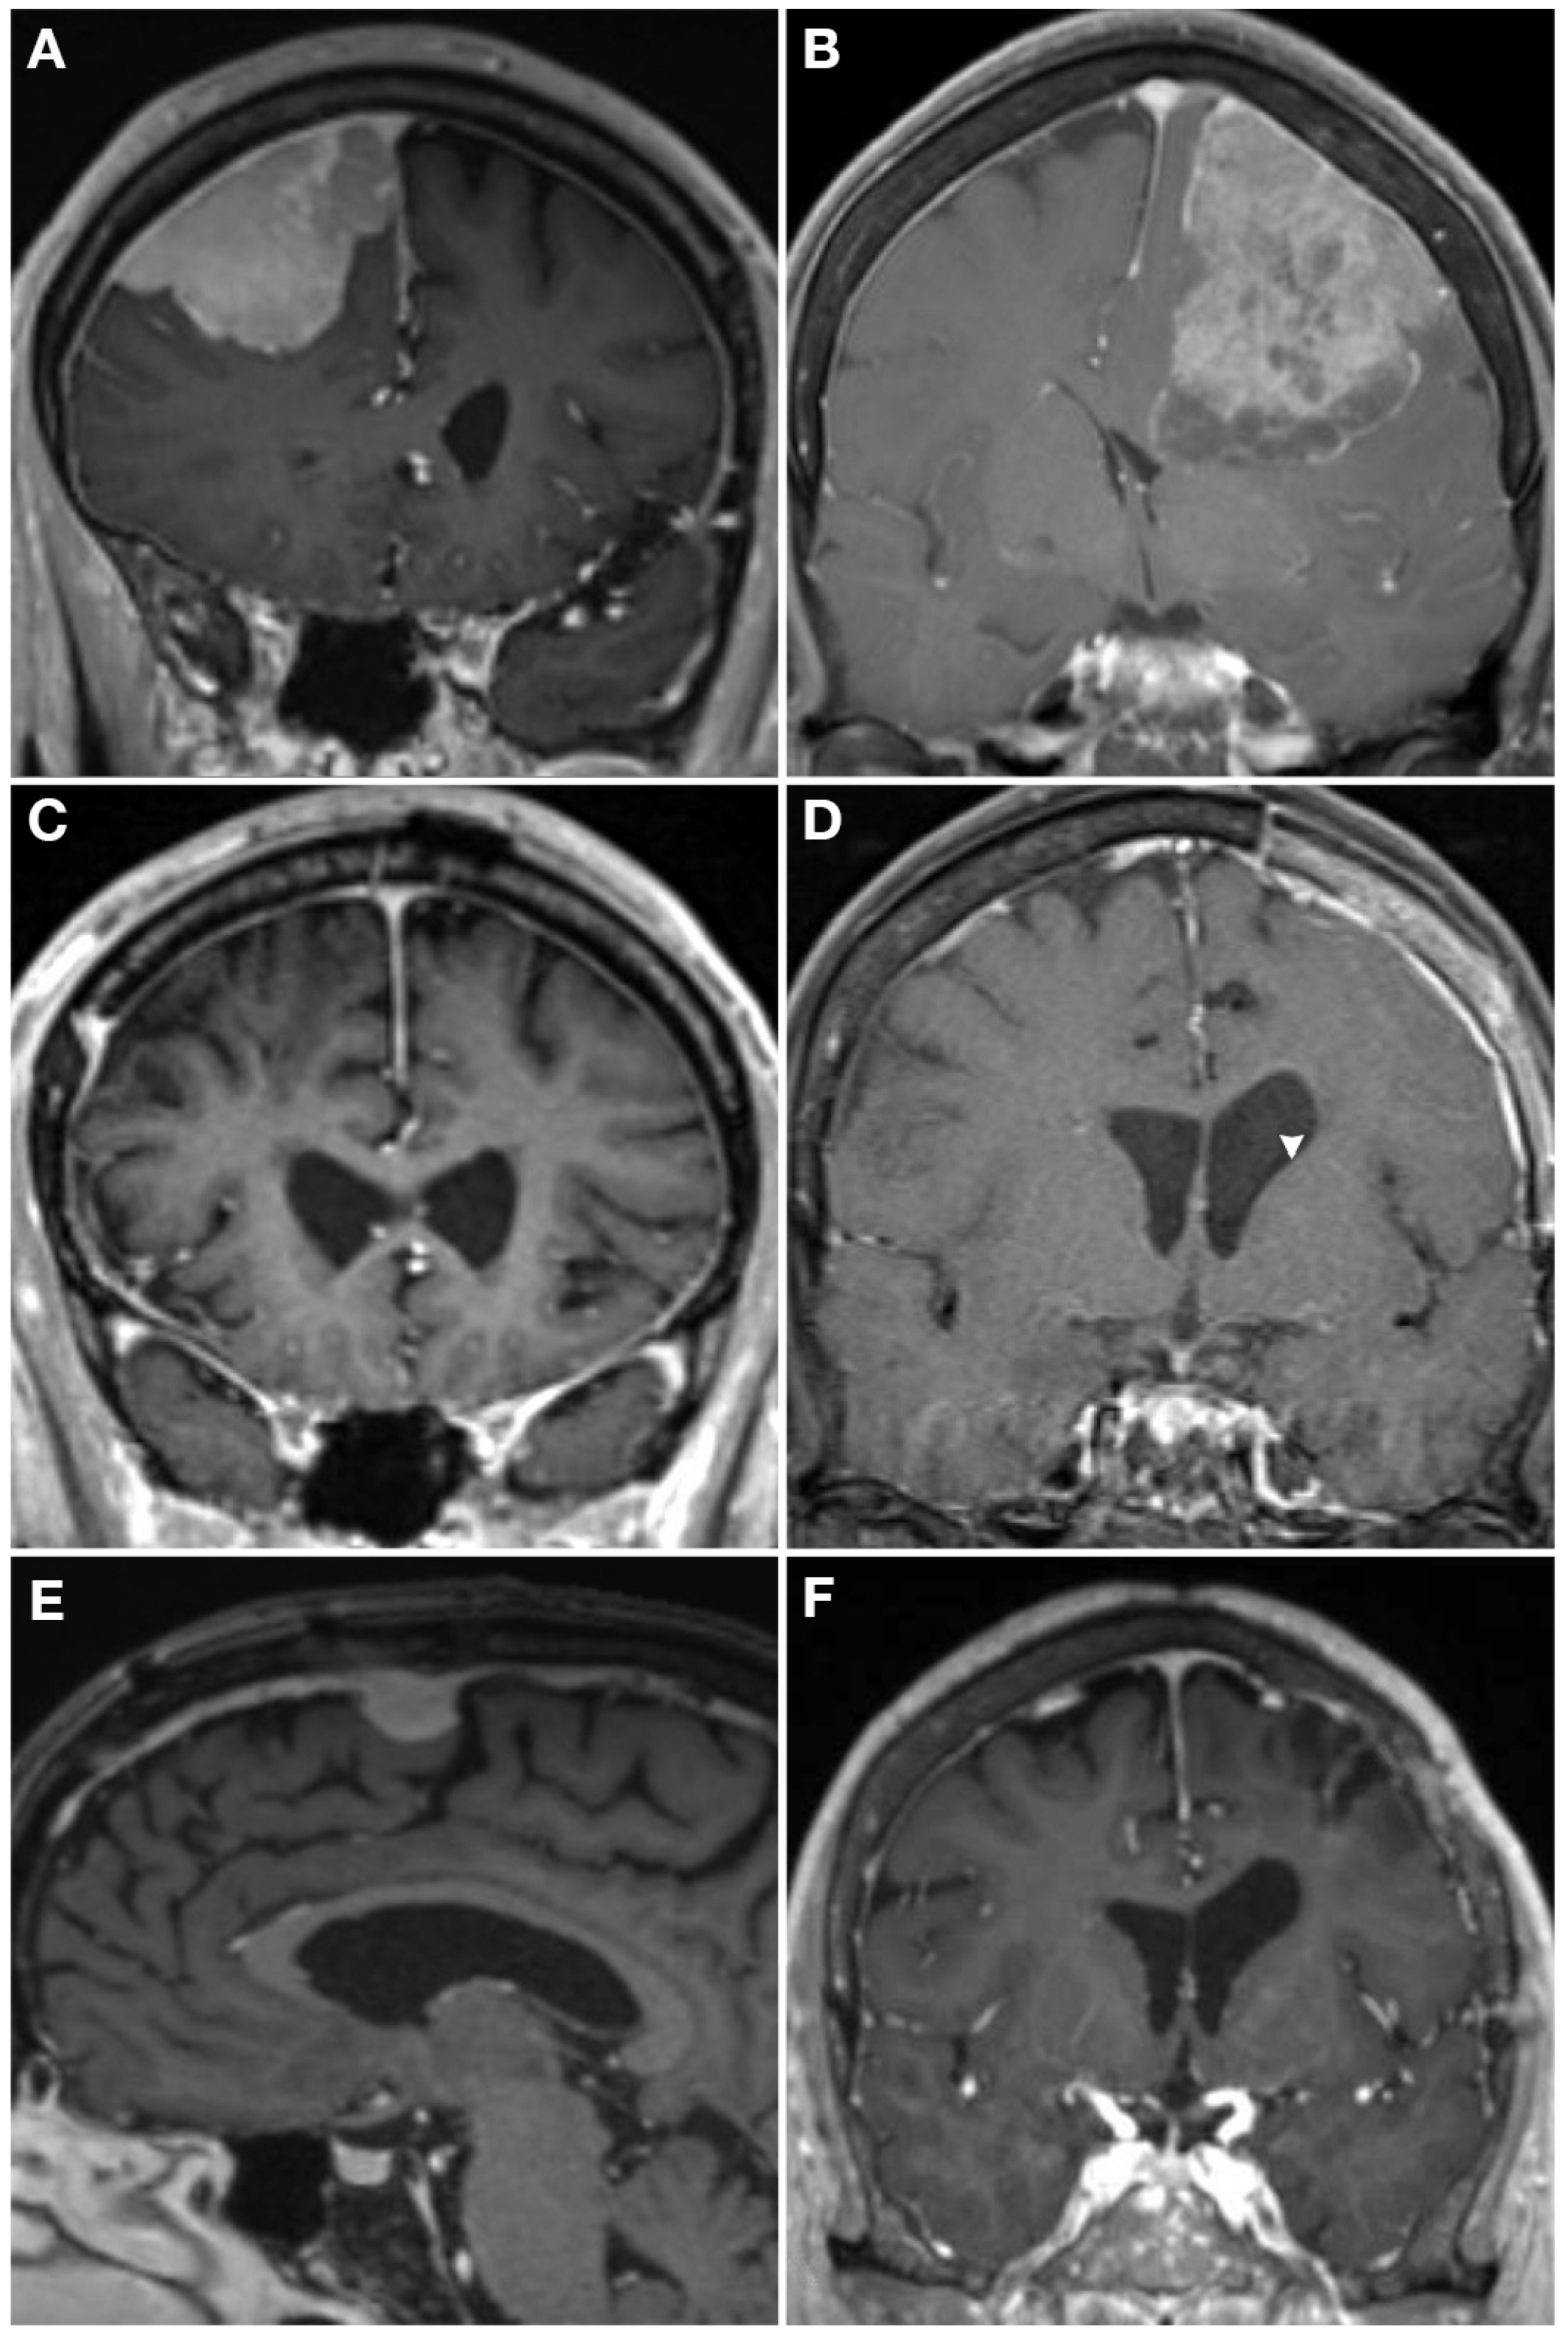

Figure 4.

Case examples demonstrating how molecular profiling can inform care. T1 post-contrast MRI from two WHO grade 2 meningiomas (A,B) who both presented with a seizure and underwent gross total resection (C,D). The patient on the left had a hypermitotic methylation profile and chromosome losses at 1p, 6, 14, haplo-insufficiency of CDKN2A, and 22q, making it a Driver et al. integrated grade 3 tumor, with a high Chen et al. gene expression risk score. He underwent 59.4 Gy adjuvant radiotherapy and had an in-field recurrence (E) at 15 months post-operative. The patient on the right also had a WHO grade 2 meningioma that had an immune-enriched methylation profile and chromosome 8 loss with haplo-insufficiency of chromosome 22, making it a Driver et al. integrated grade 1 tumor [86], and had a low Chen et al. gene expression risk score [126]. She was observed given the favorable molecular profile without adjuvant radiotherapy and had no recurrence at 2 years post-operative (F).